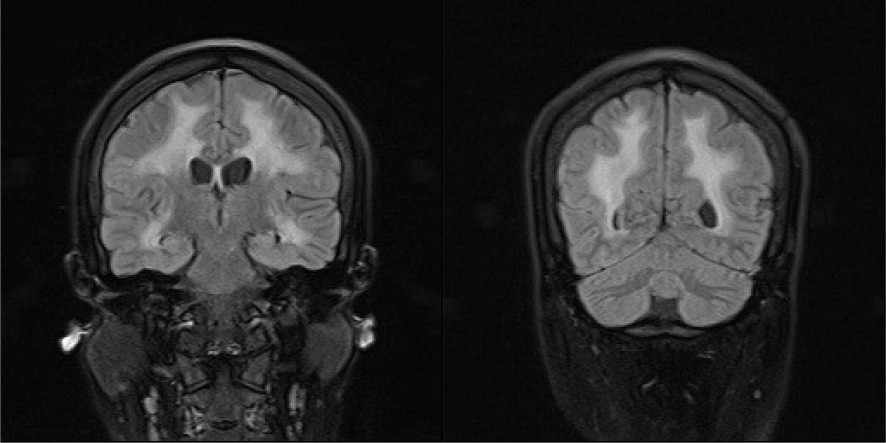

颅脑MRI平扫 + DWI + SWI (图2):双侧额颞顶枕叶、侧脑室旁白质信号异常。

Figure 2. Patient’s cranial magnetic resonance imaging

2. 患者颅脑磁共振

LAMA2-MD患者出生6个月后均出现脑白质异常,主要累及脑室旁和皮质下白质,表现为头颅MRI脑室周围及U形纤维白质大片长T1、长T2信号,而胼胝体和内囊不受累,但临床上很少出现症状,大部分患者智力正常,极少数伴有学习障碍[7]。约6%~8%患者出现癫痫,部分性和全面性发作均存在[7],少数大脑皮质发育不良患者伴难治性癫痫[2]。本患者在13岁出现癫痫发作,表现为全面性发作及复杂部分性发作,抗癫痫治疗效果欠佳,提示难治性癫痫存在,系CMD1A少见并发症。